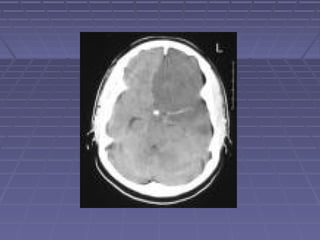

 TAC de cráneoTAC de cráneo si: persisten o aumentan lassi: persisten o aumentan las

manifestaciones clínicas, se sospechamanifestaciones clínicas, se sospecha

herniación, persiste la fiebre.herniación, persiste la fiebre.

 TC: hidrocefalia, lesiones vasculares,TC: hidrocefalia, lesiones vasculares,

tuberculomastuberculomas